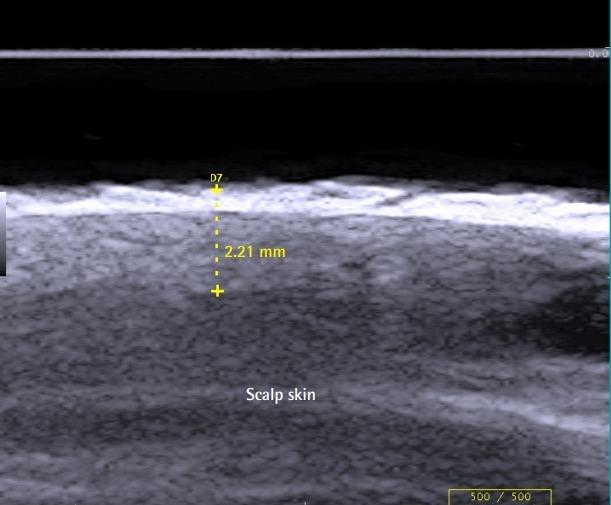

Two layers corresponding to a split-thickness skin graft (SSG) and a split-thickness dermal graft (SDG) were harvested from the scalp using a Zimmer dermatome during the same procedure. Healing of the scalp donor site, reason for recipient site grafting, and the percentage of graft loss were evaluated.

在同一手术过程中,使用 Zimmer 取皮刀从头皮获取相当于中厚皮片(SSG)和中厚真皮片(SDG)的两层组织。评估头皮供区的愈合情况、受区植皮的原因以及植皮丢失的百分比。